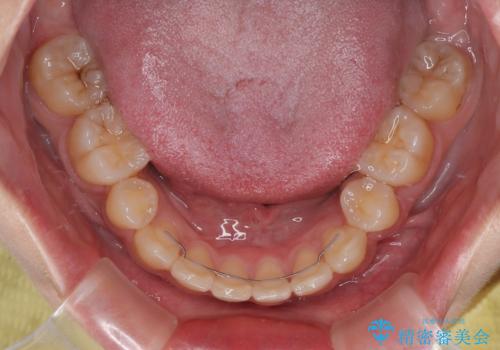

- 矯正装置

- メタルブラケット

第二小臼歯抜歯の治療となったため、やや時間はかかりましたが、概ね予想通りの期間で治療を終えることができました。